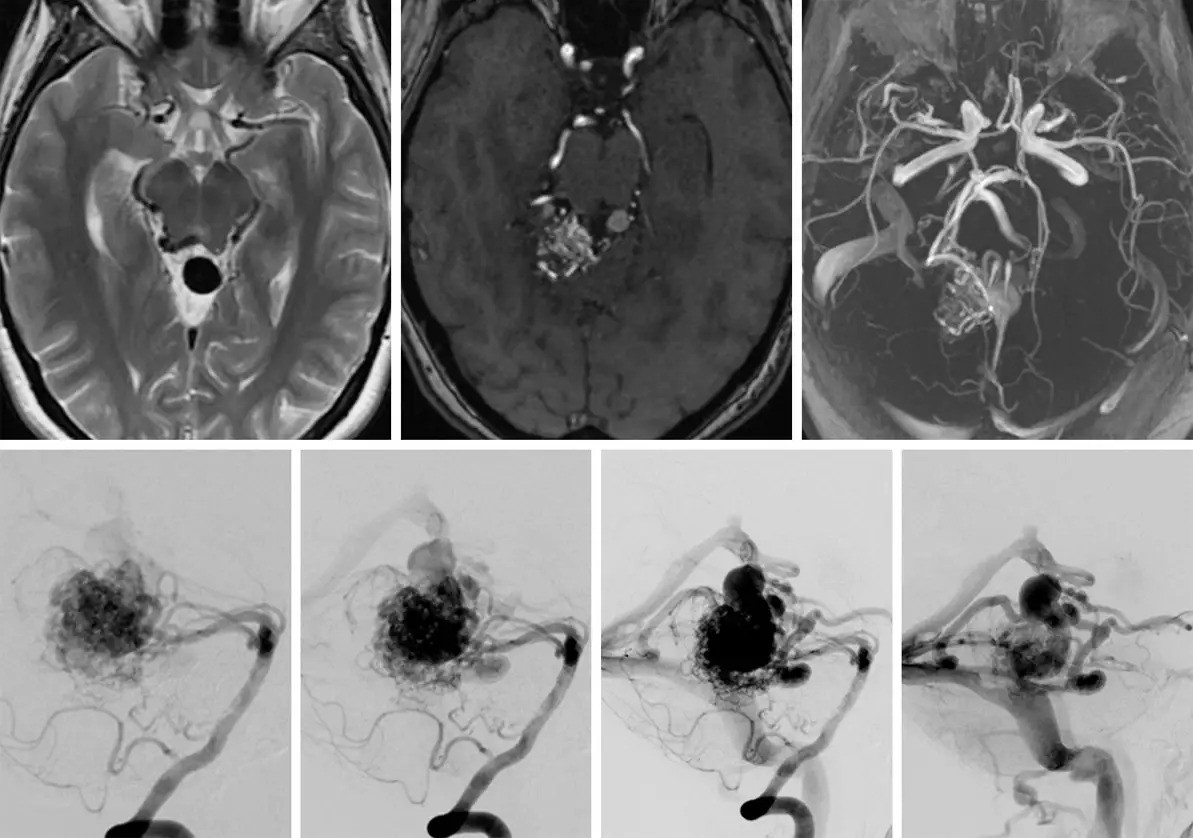

images

We specialize in the most challenging AVM cases, including:

•  Brainstem AVMs

•  Large or high-grade AVMs (Spetzler-Martin Grade III-V)

•  AVMs previously deemed "inoperable"